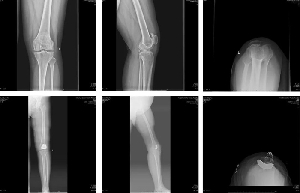

關(guān)節(jié)運動一科成功開展魯南地區(qū)首例髕股關(guān)節(jié)置換術(shù)